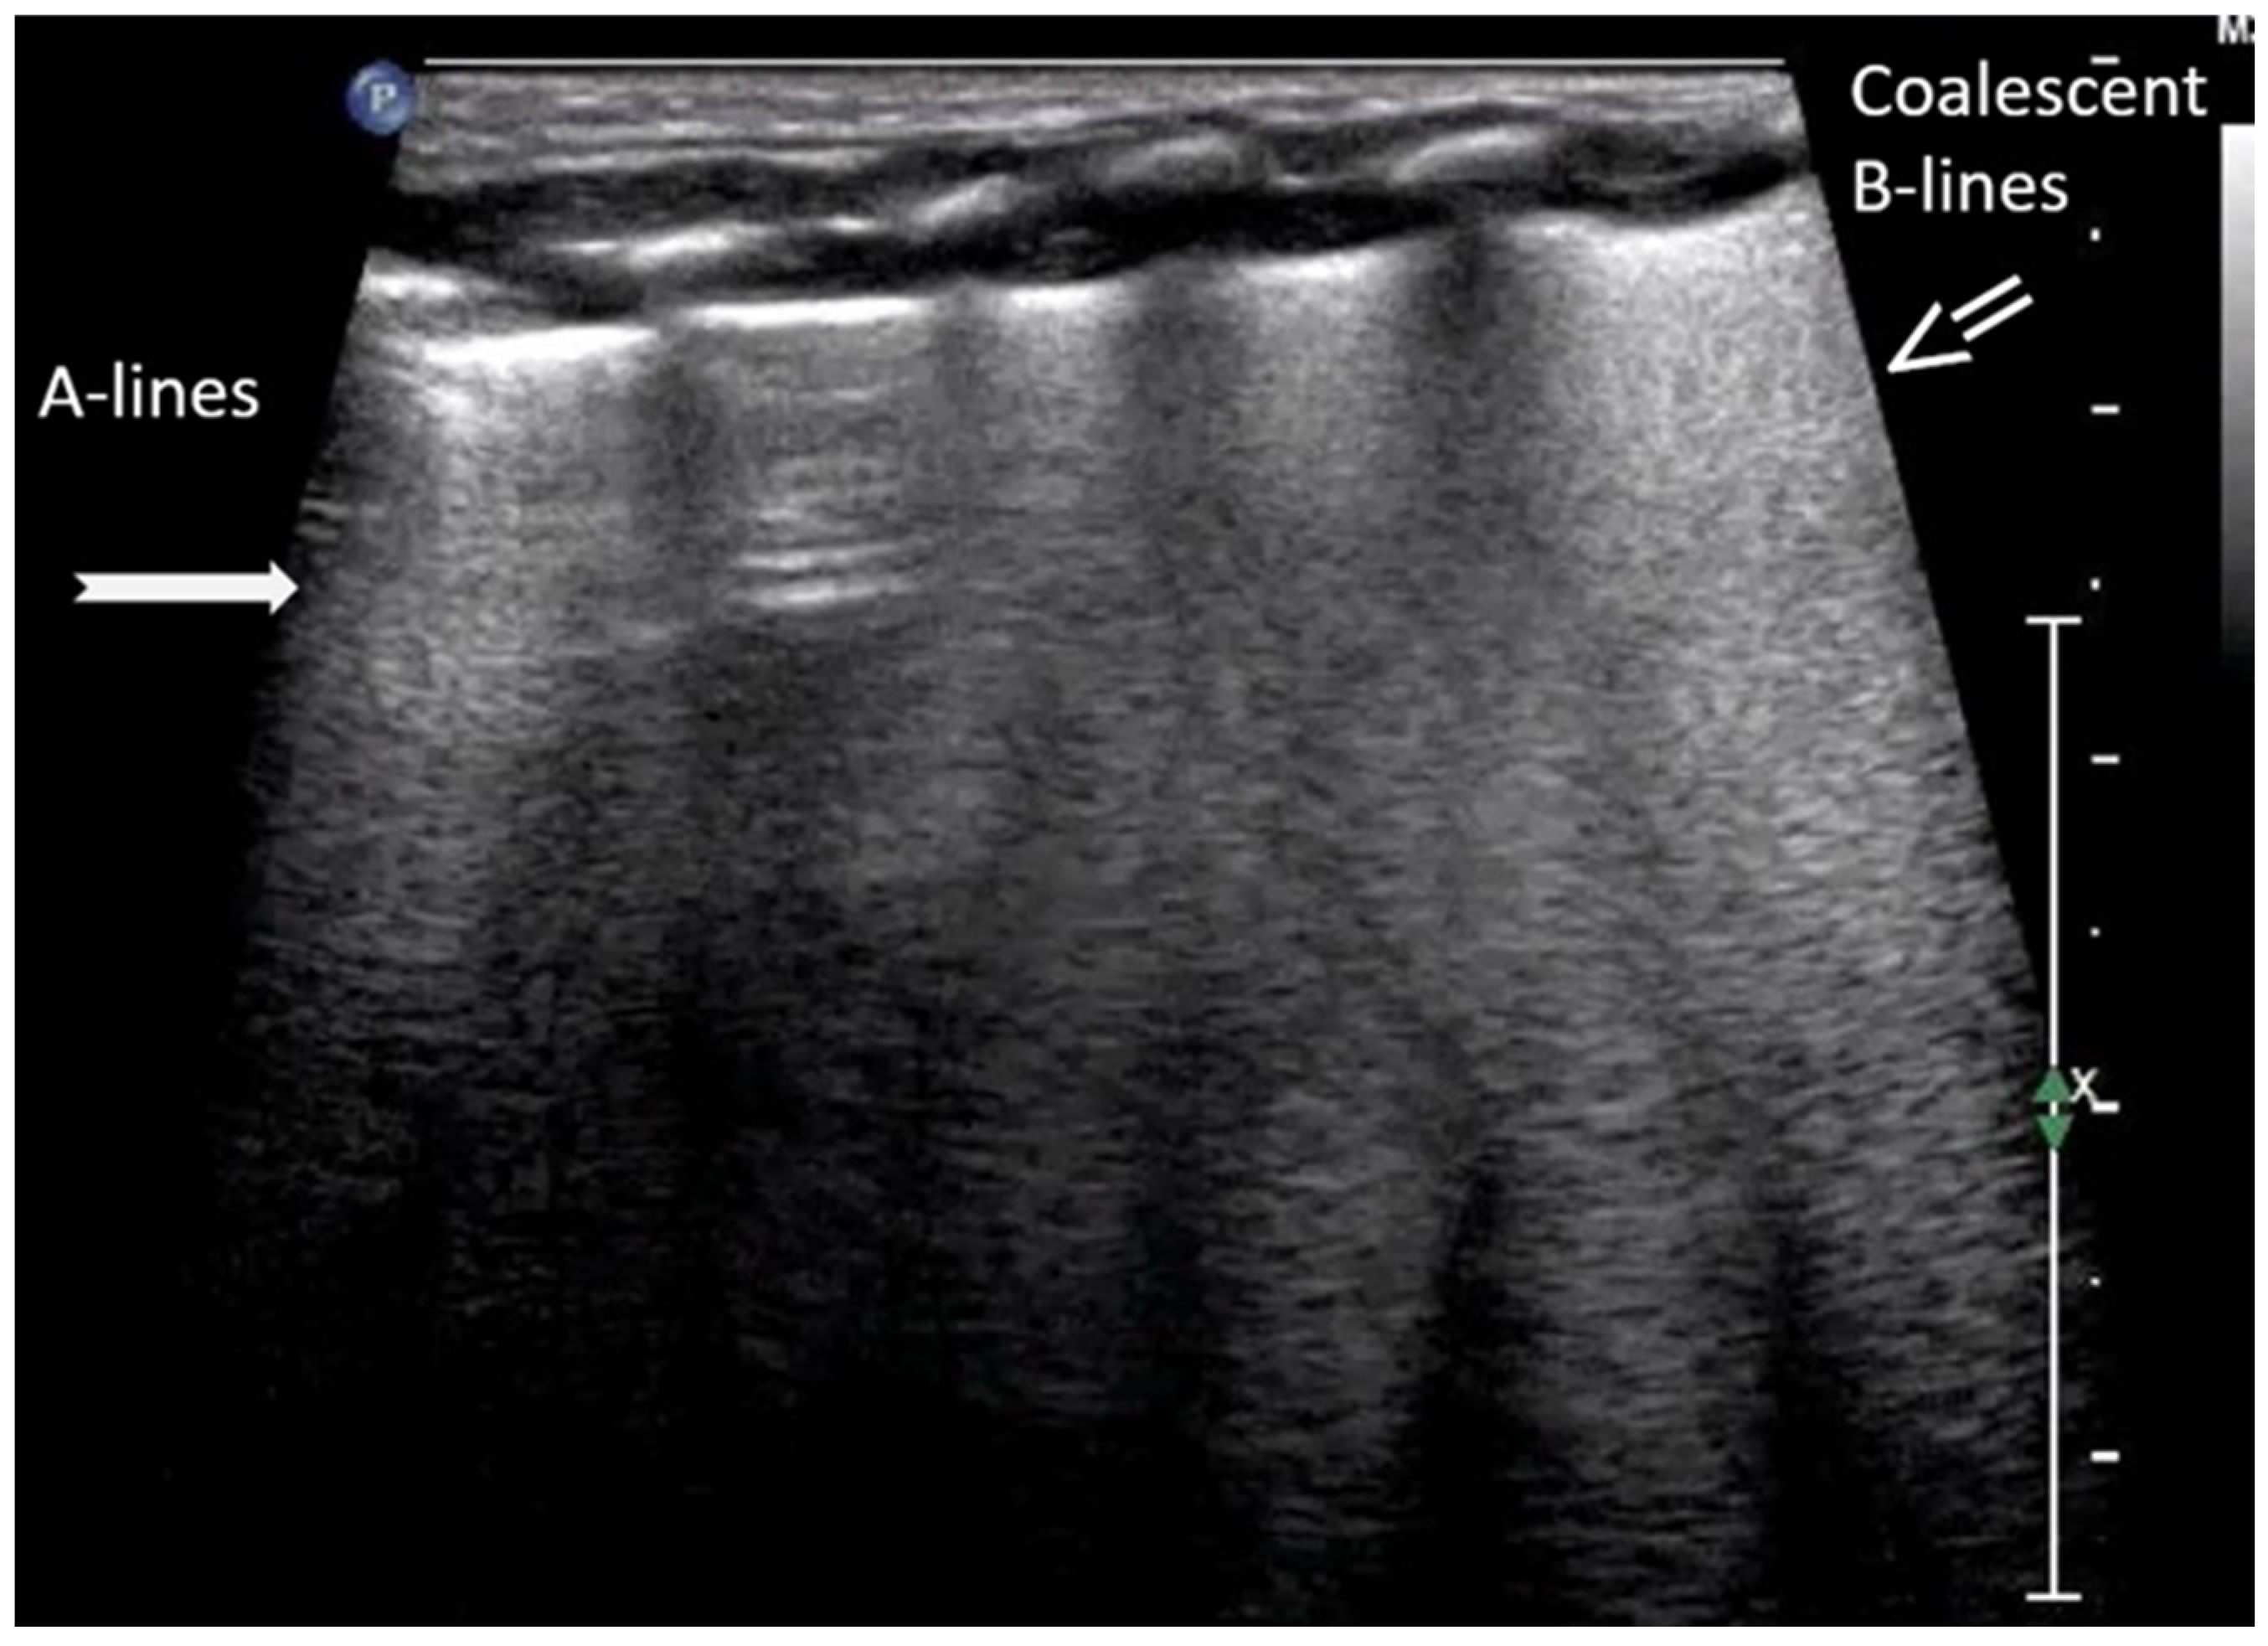

3.1.2. B-Lines

3.1.3. Pleural Line